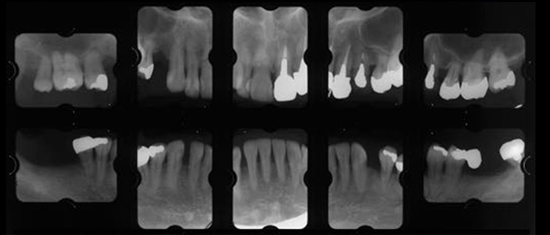

治療前01

治療前02